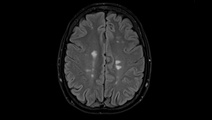

Studying Cortical Lesions in MS: Future Research Directions

NeuroFrontiersStudying Cortical Lesions in MS: Future Research Directions